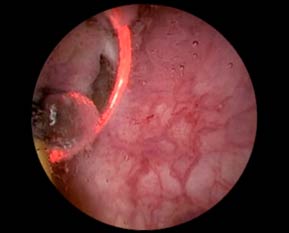

Figura 1. Aspecto endoscópico da lesão tumoral em bexiga.

O diagnóstico se dá por exames de imagem (ultrassonografia e uro-tomografia) e cistoscopia com avaliação histológica do material ressecado, sendo este o método considerado padrão-ouro no diagnóstico do câncer de bexiga.